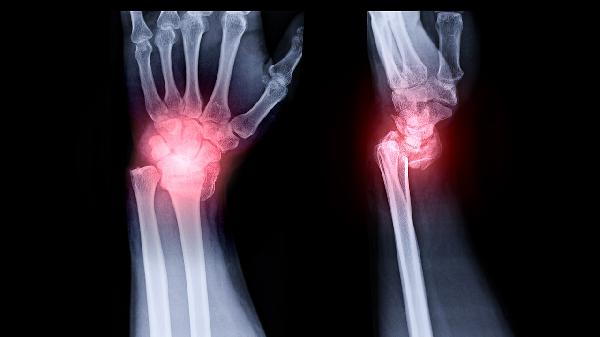

反应性关节炎是一种由感染引发的自身免疫性疾病,通常发生在感染后的2-4周内。常见感染源包括肠道、泌尿道或呼吸道感染。症状主要表现在关节疼痛、肿胀和僵硬,常伴随发热和疲劳。治疗方法包括抗生素治疗以清除感染源,抗炎药物减轻炎症,如布洛芬、萘普生,物理治疗帮助恢复关节功能。

强直性脊柱炎是一种慢性炎症性关节病,主要影响脊柱和骶髂关节。症状包括持续的背部疼痛和僵硬,早晨尤为明显,严重时可能导致脊柱弯曲和活动受限。治疗上,常用非甾体抗炎药如阿司匹林、吲哚美辛,生物制剂如肿瘤坏死因子抑制剂,以及物理治疗和运动疗法,帮助维持脊柱的灵活性和改善姿势。